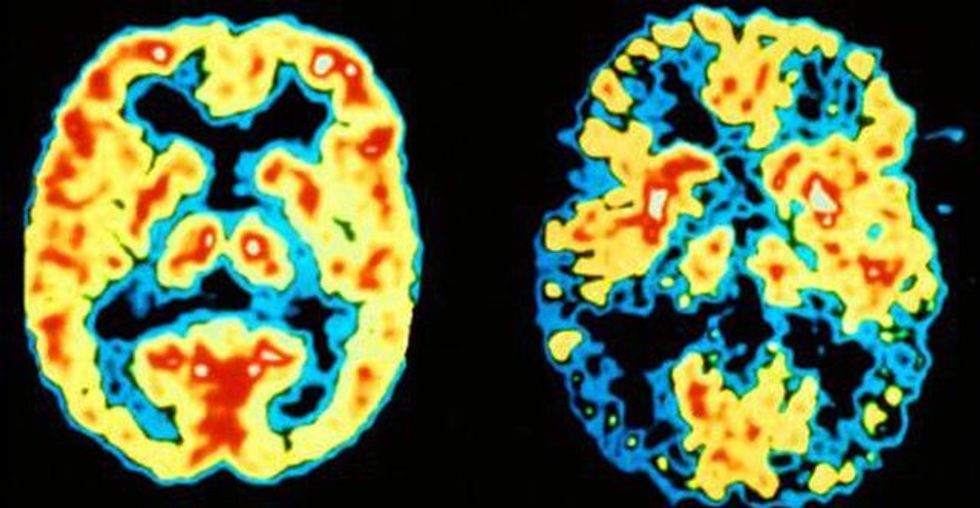

"Nëse jeni në një partneritet shumë të lumtur, duke kaluar më shumë kohë me njeriun e zemrës, kjo do të nxisë sistemin e dopaminës, duke ju dhënë optimizëm, energji dhe motivim, forcimin e sistemit imunitar dhe rritjen e pragut të dhimbjes", thotë Fisher.

"Nëse jeni i/e bllokuar në një partneritet që nuk funksionon, kjo është shumë stresuese dhe stresi kronik zvogëlon sistemin e dopaminës dhe mund t'ju bëjë të ndjeheni letargjikë dhe në depresion", shpjegon Fisher.